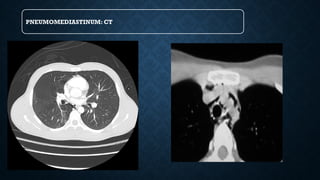

PNEUMOMEDIASTINUM: CT

PNEUMOMEDIASTINUMWITH SUBCUTANEOUS EMPHYSEMA